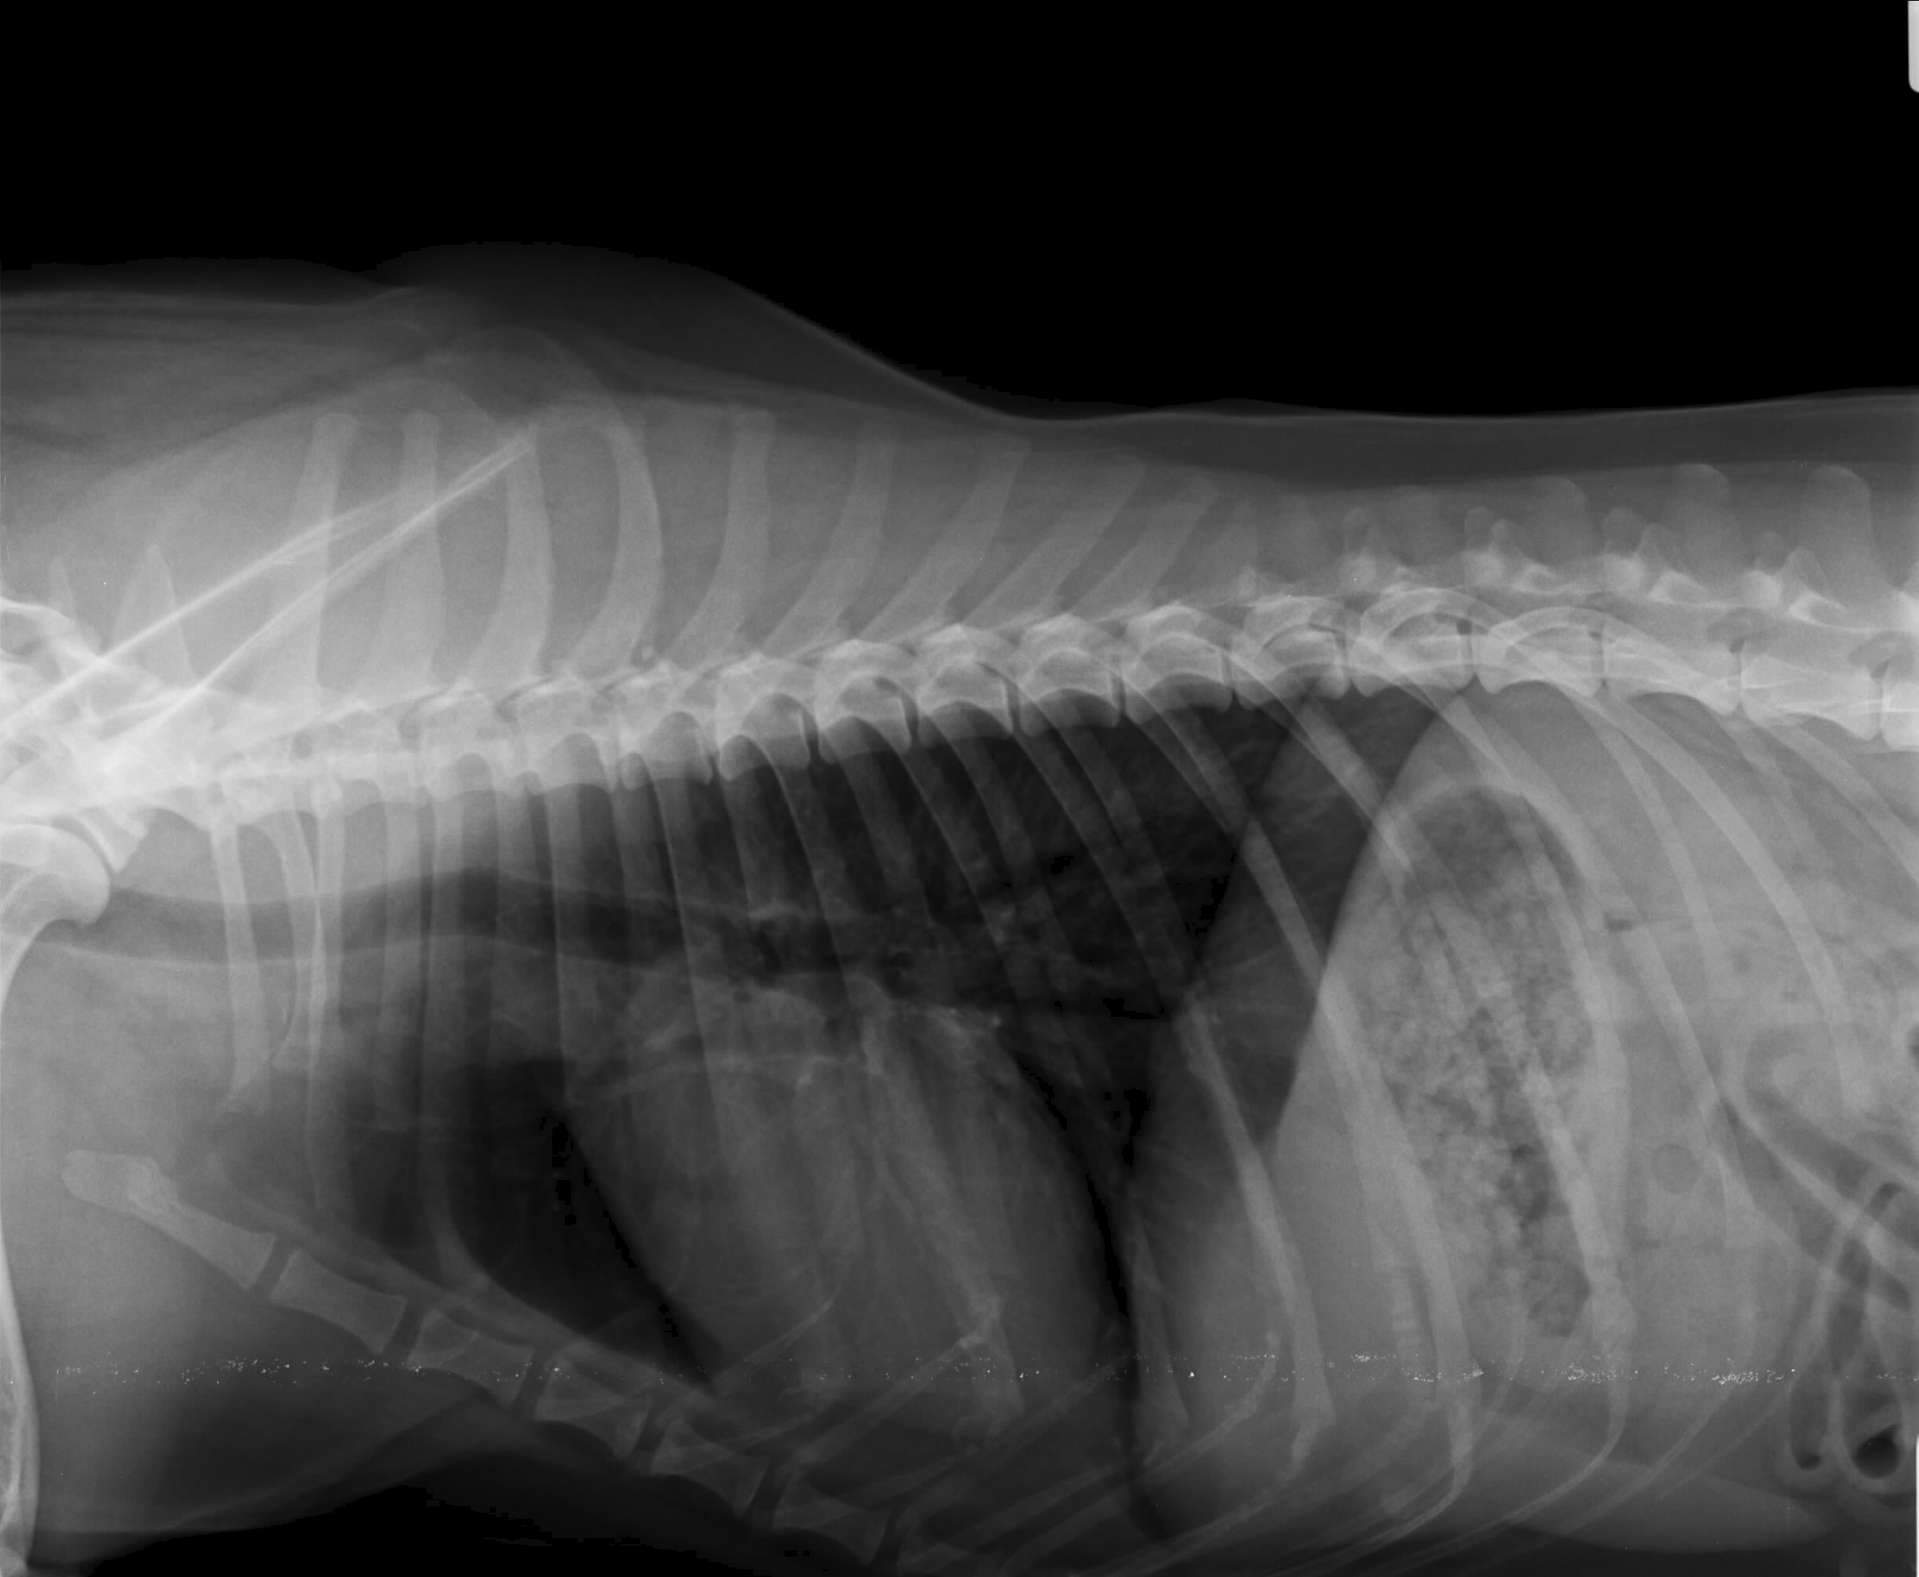

Был посещен веткабинет и сделан: биохимический анализ крови; боковой рентген грудной клетки (легкие). По поводу "язвочки" сказали кожное, обрабатывать хлоргексидином и левомиколью.

Анализ хороший, рентген вопрос. Необходимо стороннее мнение.

5) что у нас с трахеей? Может ли быть врожденное или ушиб в детстве? Подобрана собака в 1,5-2 месяца.

Нам предположили что под трахеей метостаз

Снимок и фотографию прилагаю. Спс за внимание и любые советы!